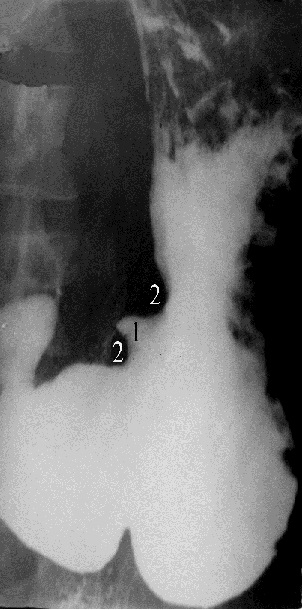

Ограниченное увеличение тени, обусловленное язвой, называется «ниша». Если ниша выходит на контур органа (рис. 13), то она имеет вид выступа треугольной или неправильной формы (1). Выше и ниже ниши часто определяется вогнутое вдавление – симптом „язвенного вала” (2). Морфологически в основе его - спазм стенки около язвы, отек слизистой оболочки и рубцовые изменения. За счет наличия язвенного вала создается впечатление большей глубины ниши. Если ниша не выходит на контур, то она определяется в виде контрастного пятна на слизистой оболочке – «ниша на рельефе» (рис. 14). Язвенный вал в подобных случаях представлен кольцевидным дефектом рельефа вокруг бариевого пятна. Язвы чаще определяются в желудке и луковице 12-перстной кишки.

Рис. 13. Рентгенограмма желудка в прямой проекции в вертикальном положении больного. В нижней трети тела по малой кривизне определяется ниша (описание в тексте). Язвенная болезнь желудка.

В средней трети тела желудка на фоне рельефа слизистой оболочки определяется бариевое пятно. Вокруг – дефект наполнения, обусловленный язвенным валом. Язвенная болезнь желудка.